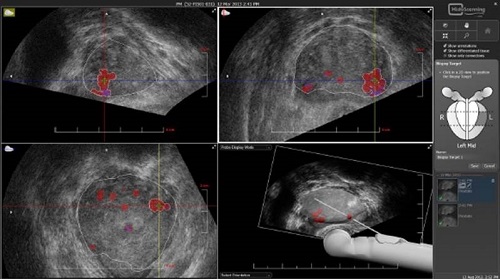

Только после соблюдения рассмотренных выше рекомендаций может проводиться процедура биопсии, поскольку точная оценка зависит от правильного подхода к подготовке. Обследование осуществляется натощак утром. Перед исследованием органа в область прямой кишки вводят анестезирующее средство (обычно в качестве такового используют «Лидокаин»). Через определенное время после местной анестезии вводят ультразвуковой датчик с насадкой, специально предназначенный для осторожного введения иглы. Посредством этой иглы берутся образцы из определенных точек органа.

Биопсия предстательной железы осуществляется под контрольным УЗИ с целью определить точки взятия образцов. Больные легко проходят процедуру, иногда могут проявляться неприятные ощущения, длящиеся недолго. Взятые образцы передаются в соответствующую лабораторию для проведения исследований, позволяющих определить стадию развития заболевания.